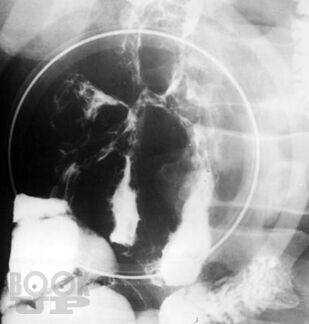

В учебном пособии «Свищи желудочно-кишечного тракта» освещены вопросы классификации, клинической картины, диагностики свищей желудочно-кишечного тракта. Предложен лечебно-диагностический алгоритм при данной патологии. Особое внимание в методическом пособии отведено принципам консервативного и оперативного лечения наружных желудочнокишечных свищей.